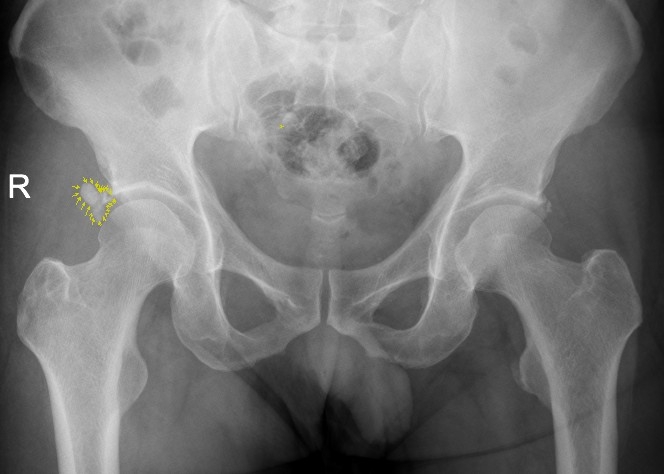

該患者為男性患者,47歲。右髖部疼痛7個多月,曾斷續(xù)就醫(yī),未明確診斷,疼痛時緩時重。入院前兩天,右髖部劇烈疼痛,患髖不能伸直,只能左側(cè)臥位,謂之“坐臥不寧”,需家人攙扶下才能勉強行走。經(jīng)臨床經(jīng)驗豐富的骨三科主任、主任中醫(yī)師李彬以“右髖關(guān)節(jié)盂唇病變”收入住院治療,經(jīng)X光核磁共振檢查,患者右髖關(guān)節(jié)盂唇鈣化。

X片顯示盂唇鈣化病灶